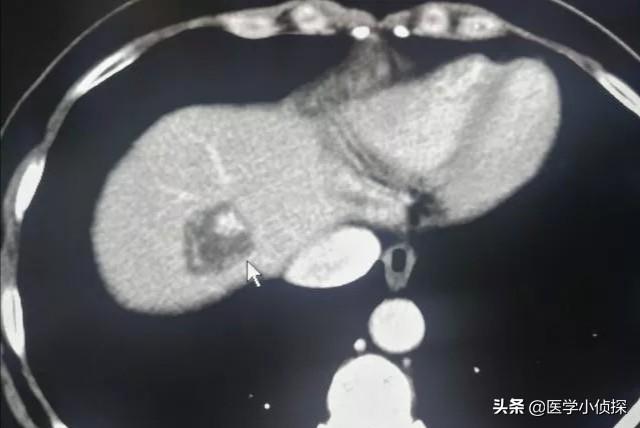

首先,目前对于肝囊肿的形成,未发现的原因,通常认为它属于先天性的肝脏异常囊,可以在我们人的一生中的任何时候发生,起源于错构组织,囊肿内部为就是囊液,就跟我们大家平时手上或者脚上磨出水泡差不多,正因为有这一种“水泡”存在,所以我们的B超,CT和核磁(MRI)都可以发现诊断(如下图,白色箭头所指)!

那么对于肝囊肿如何诊断呢?其实对于肝囊肿的诊断,最主要还是依靠影像学检查,首选就是超声检查,我们很多体检患者发展肝囊肿,往往都是通过超声发现的,在超声上,肝囊肿表现为肝实质内出现一个或多个圆形或类圆形的无回声区,壁薄,边缘光整,病灶内部也检测不到血流信号;除了超声检查之外,CT检查和MRI检查也可以发现肝囊肿的存在,而且还可以对一些复杂肝囊肿做出诊断。CT上,一般单纯性的肝囊肿主要表现为圆形的低密度影,边界清楚,内部密度一般比较均匀,CT值大约在0-20HU。如果做了增强扫描,那么病灶是不会出现任何强化的。